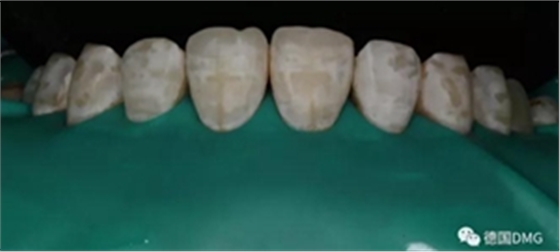

1,術前照片,全口氟斑牙,前牙表面釉質白堊色+黃色斑點+凹坑缺損。

術前正面?zhèn)让嬲掌?/span>

2,使用紅標45μm微米和黃標25μm粒度車針仔細緩慢打磨去除釉質表面高氟鈣化的斑塊和釉質凹坑0.05-0.1mm后,車針打磨后要再使用低速慢機用矽粒子拋光去除釉質表面浮釉(松風矽粒子、樹脂拋光輪),下圖是微打磨后。

(下圖是上頜打磨后與下頜術前未研磨對比,區(qū)分打磨效果和目的)